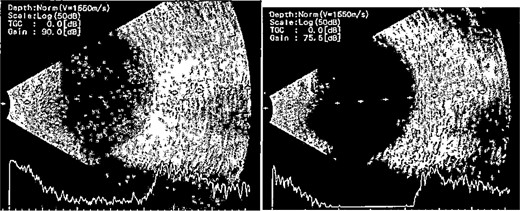

Patient 3: A 63-year-old Saudi female reported pain and decreased vision in her right eye. On examination 4 days post-surgery, her vision was PL. Examination findings included severe conjunctival injection (Fig. 5). B-scan (Fig. 6). Treatment included vitreous tap and intravitreal antibiotics.

B-scan ultrasound demonstrating mild to moderate vitritis in endophthalmitis case for patient 3.